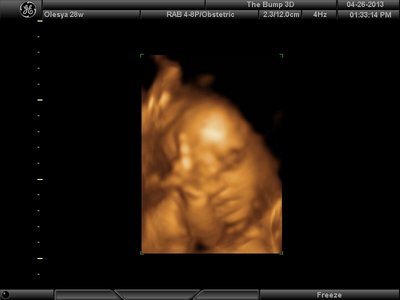

А я вчера на 3Д УЗИ ходила. Моя звезда закрывалась в еми 4мя конечностями. Просто пополам сложилась и спала себе сладко. УЗИстка провела со мной час, кое-как расшевелили маленькую, но ручка была постоянно на мордашке и засыпала она почти сразу снова. Я и на мяче прыгала и живот трясла. В конце более-менее фото вышли, но качество меня не порадовало. Возможно фри оф чардж еще раз переделают. Со средней фотки были отличного качества, а эти сплошное разочарование. Вот тут что-то более-менее еще. Главное пальчик оттопырила так смешно, мол минуточку. Вообще немного жутковатые фотки..хаха

| Вложения: |

image.jpg [ 47.86 КБ | Просмотров: 1440 ]